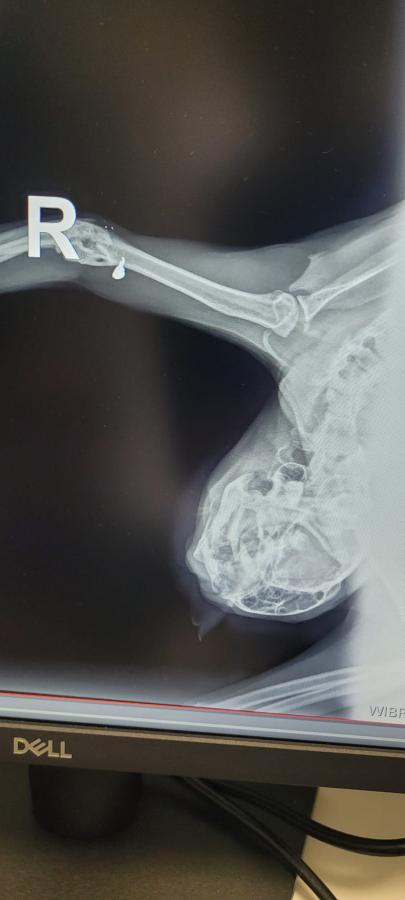

Opis galerii zdjęć: Zdjęcia kota Śnieżka, postrzelonego na ul. Białowieskiej, przed i po operacji usunięcia śrutu z łapki. Oferowanie nagrody za informacje o sprawcy oraz poszukiwanie rodziny adopcyjnej dla kota. Podkreślenie ochrony prawnej zwierząt i konieczności zgłaszania takich aktów do Stowarzyszenia Pan Kot.